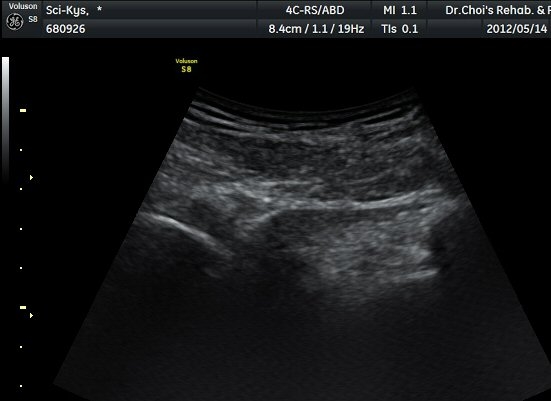

Á¤»óÃø(±×¸² 6, 7)°ú ºñ±³Çϸé Á°ñ½Å°æÀÇ ³»Ãø ÀüÀ§°¡ ¶Ñ·ÈÇÏ´Ù.